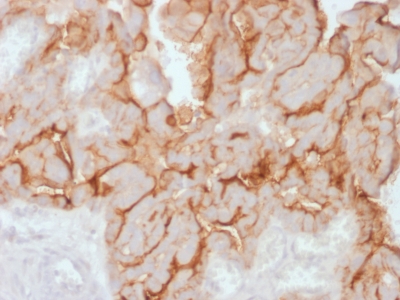

IHC (Immunohistochemistry)

(Formalin-fixed, paraffin-embedded human Ovarian Carcinoma stained with MUC16 Rabbit Recombinant Monoclonal Antibody (OCA125/2349R).)